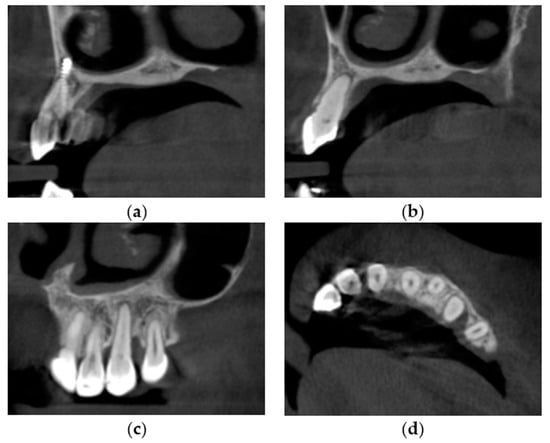

- Directorate-General for Energy (European Commission). Cone Beam CT for Dental and Maxillofacial Radiology: Evidence Based Guidelines; Publications Office of the European Union: Luxembourg, 2012; ISBN 978-92-79-24808-5. [Google Scholar]

- Stasiak, M.; Adamska, P. Should Cone-Beam Computed Tomography Be Performed Prior to Orthodontic Miniscrew Placement in the Infrazygomatic Crest Area?—A Systematic Review. Biomedicines 2023, 11, 2389. [Google Scholar] [CrossRef] [PubMed]

| October 2017 | PDCs’ surgical exposure—open technique; brackets bonded on PDCs; MIs tomas®-pin SD 06 (Dentaurum, Ispringen, Germany) inserted in the palatal alveolar region; 0.016″ × 0.022″ TMA cantilevers activated in distal and downward direction (50 g) (Figure 6a,b). |

| November 2017 | Visible orthodontic movement—exclusion of primary ankylosis (Figure 6c). |

| December 2017 | Increased mobility and tenderness of PDCs, dismantlement of cantilevers, button on the buccal side of UL3 (derotation), power chains to move the teeth (Figure 6d). |

| January 2018 | Teeth stability improved; 0.017″ × 0.025″ TMA cantilever with activation in downward and buccal directions for UR3, power chain for distal movement and derotation of UL3. |

| February 2018 | Button on the buccal side of UR3 (derotation), power chains for distal movements and derotations (Figure 6e). |

| April 2018 | Extraction of the upper right deciduous canine due to the collision with movement of UR3; 0.017″ × 0.025″ TMA cantilever activated for buccal movement of UR3 (50 g) (Figure 6f). |

| June 2018 | Partial fixed upper SS appliance Equilibrium® 2 0.022″ in Roth prescription (Dentaurum, Ispringen, Germany), 0.016″ NiTi wire, continuous metal ligature to create space for UL3; cantilever activation (Figure 6g). |

| August 2018 | Bracket on tooth no. 24; 0.016″ NiTi wire and open coil spring to create space for UL3; extraction of the upper left deciduous canine. |

| October 2018 | New MI tomas®-pin SD 08 (Dentaurum, Ispringen, Germany) was inserted in the buccal surface of left alveolar ridge; 0.017″ × 0.025″ TMA cantilever for buccal movement of UL3 (50 g) (Figure 6h). |

| November 2018 | Mobility of the buccal alveolar MI, the miniscrew was tightened and left to stabilize for a month; tooth no. 55 was extracted due to progressive reinclusion. |

| December 2018 | Buccal alveolar MI was lost and new MI tomas®-pin SD 10 (Dentaurum, Ispringen, Germany) was placed in the IZC; 0.017″ × 0.025″ TMA cantilever with buccal activation for UL3 (50 g). |

| February 2019 | Inflammation and submucous abscess in the IZC; MI removal; antibiotic. |

| April 2019 | New MI tomas®-pin SD 10 (Dentaurum, Ispringen, Germany) was inserted in the palatal suture and used as a direct anchorage with 0.017″ × 0.025″ SS cantilever and power chain for buccal movement of UL3 (50 g); 0.016” SS wire and bend-out for UR3 (Figure 6i). |

| May 2019 | Overcorrection of UR3 transversal relationship, 0.018″ SS wire and bend-out for tooth no. 22, new power chain from cantilever to UL3 for its buccal movement. |

| July 2019 | Tooth no. 22 in correct sagittal relationship; MI in the palatal suture used as an indirect anchorage: 0.017″ × 0.025 SS connection wire with tooth no. 24, 0.017″ × 0.025″ cantilever with buccal activation for UL3 (50g); 0.017″ × 0.025″ Cooper NiTi wire (Figure 6j,k). |

| March 2020 | The correct position of UL3; tooth no. 24 showed significant mobility; control panoramic X-ray: root resorption of tooth no. 24 (Figure 7); no possibility to conduct control visits on a regular basis due to COVID-19 pandemic—next appointment took place in November 2020. |